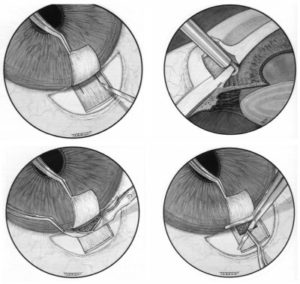

Η πιο συχνή αντιγλαύκωματική επέμβαση είναι η τραμπεκουλεκτομή. Σ αυτήν δημιουργούμε στο άσπρο του ματιού (στο σκληρό χιτώνα) ένα καλυμμένο τούνελ που παροχετεύει το υδατοειδές υγρό από το εσωτερικό του ματιού σε μια μικρή φυσαλίδα κάτω από το άνω βλέφαρο. Έτσι ελαττώνεται η πίεση του υδατοειδούς υγρού και επομένως και η πίεση στο οπτικό νεύρο η οποία προκαλεί την απώλεια της όρασης στο γλαύκωμα.

epemvasi 1

Άλλες αντιγλαύκωματικές επεμβάσεις είναι: